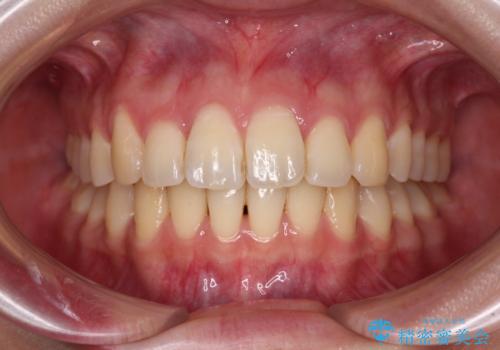

上下前歯の捻れが改善され、患者様には大変満足していただきました。